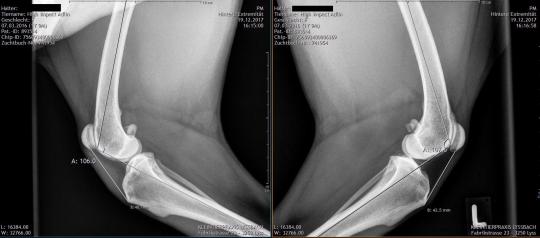

Erneut wird das verletzte Knie untersucht: Die beiden Hautwunden scheinen schön zu heilen, allerdings lässt sich nun feststellen, dass die Kniescheibensehne deutlich verdickt und schmerzhaft ist und sich weicher anfühlt als die Sehne im linken Knie. Die Patellarsehne (Ligamentum Patellae) zieht von der Kniescheibe zum Schienbein und ermöglicht dem Oberschenkelmuskel das Knie zu strecken. Röntgenaufnahmen der beiden Knie bestätigen, dass die Sehne stark verdickt ist. Unklar bleibt, ob sie gerissen oder nur stark überdehnt ist - in ersterem Fall muss das Problem zwingend chirurgisch angegangen werden. Wir überweisen Adlin deshalb zu einem MRT an eine Spezialistenklinik.

Der Verband wird jede Woche gewechselt. Langsam aber stetig beginnt die Hündin, das verletzte Bein besser zu belasten. Ein Vergleichsröntgen nach zwei Wochen zeigt, dass die Längendifferenz der rechten zur linken Sehne nicht zugenommen hat - ein Zeichen, dass auch die Überdehnung nicht weiter zugenommen hat. Nach drei Wochen wird die Schiene im Verband weggelassen, nach total 6 Wochen wird dann, wenn die Heilung weiterhin so befriedigend verläuft, auch der letzte Verband entfernt und der Hund vorsichtig stärker belastet. Zu diesem Zeitpunkt sollte die Sehnenverletzung genügend vernarbt sein, um stabil zu bleiben.